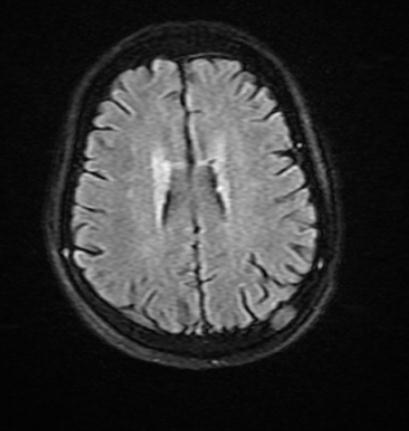

– MRI sọ não: hình ảnh ngấm thuốc xương chẩm trái theo dõi thứ phát

Hình 3: Hình ảnh chụp cộng hưởng từ sọ não |